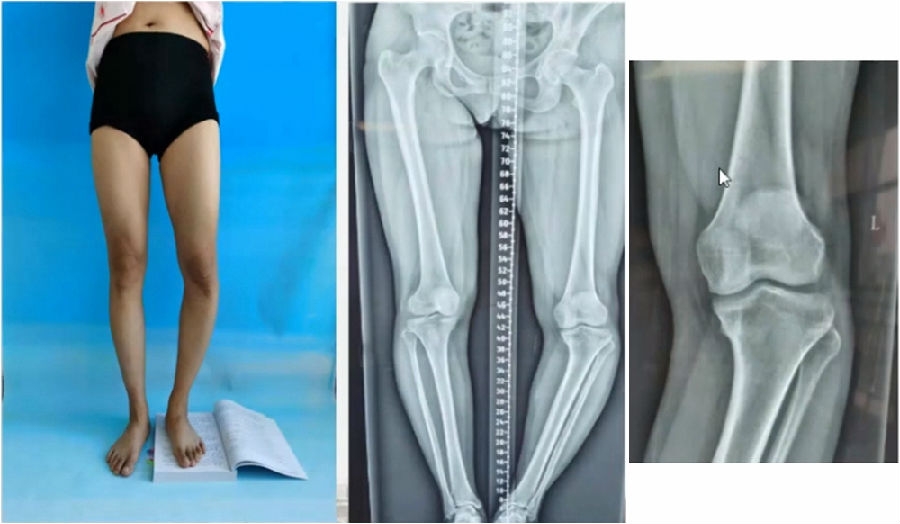

典型病例,女性,35岁,农民,左膝内翻、短缩、内旋。

术前

泰勒外固定架缓慢矫正短缩、内翻、前弓、内旋。

术中

该患者截骨后,做MAD矫正,目标MAD=0。患者术后1个月即达到设计的效果。

术后1个月